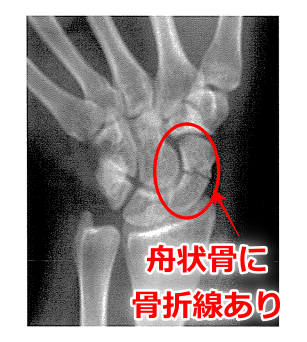

問題67 20歳の男性。サッカーで後方に左手を突いて転倒し受傷した。病院にて骨折と診断された。受傷時の単純エックス線写真を下に示す。ギプスによる保存的治療を8週間行ったが、半年の時点でも疼痛は残存している。

・受傷時の単純エックス線写真:舟状骨骨折骨折。

→本症例(舟状骨骨折)は、ギプスによる保存的治療を8週間経過した症例である。ほかの選択肢が消去できる理由もあげられるようにしよう。

4.× この骨の血流は、「近位」ではなく遠位から入る。舟状骨の血流の特徴として、遠位→近位の一方向性であり、近位端には血管が少ない。特に、近位1/3部骨折で、血流が遮断されると近位骨片の栄養が途絶し、骨癒合が遅延または不全(偽関節)となりやすい。